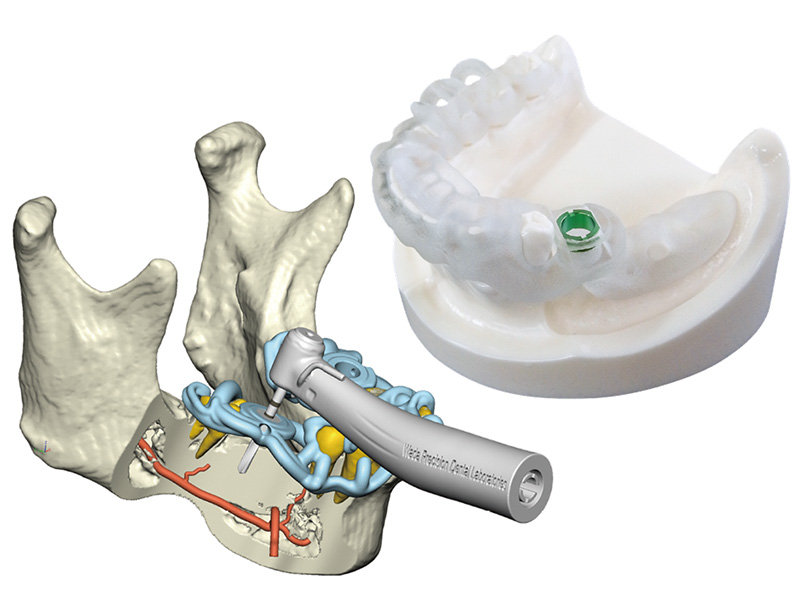

精密検査・治療計画

CT 撮影・上下歯の型取り(口腔内スキャン)などの検査を行います。

それを元にサージカルガイドを作成します。

OSSTEMによる分析とサージカルガイド作成

分析結果の説明をいたします。

必要に応じて、最新の解析診断システムのデータを基にサージカルガイドを作成します。

インプラント治療の安全性と精度を高めるために、当院では「ワンガイドシステム」を活用しています。

ワンガイドシステム

ワンガイドシステムは、CT画像から得られたデータをもとに、患者さまの顎の骨や歯周組織の状態を3Dで可視化するインプラント解析診断システムです。骨の厚みや密度、神経や血管の位置まで詳細に把握できるため、より安全で精密な治療計画の立案が可能になり、術中の誤差を最小限に抑えるサージカルガイドを作製します。

- 高精度な3Dシミュレーションにより、インプラント埋入位置・角度・深さを事前に設計

- 神経や血管の損傷リスクを回避し、安全性を大幅に向上

- 骨の状態や周囲組織の情報をもとに、患者さまごとの最適な治療計画を立案